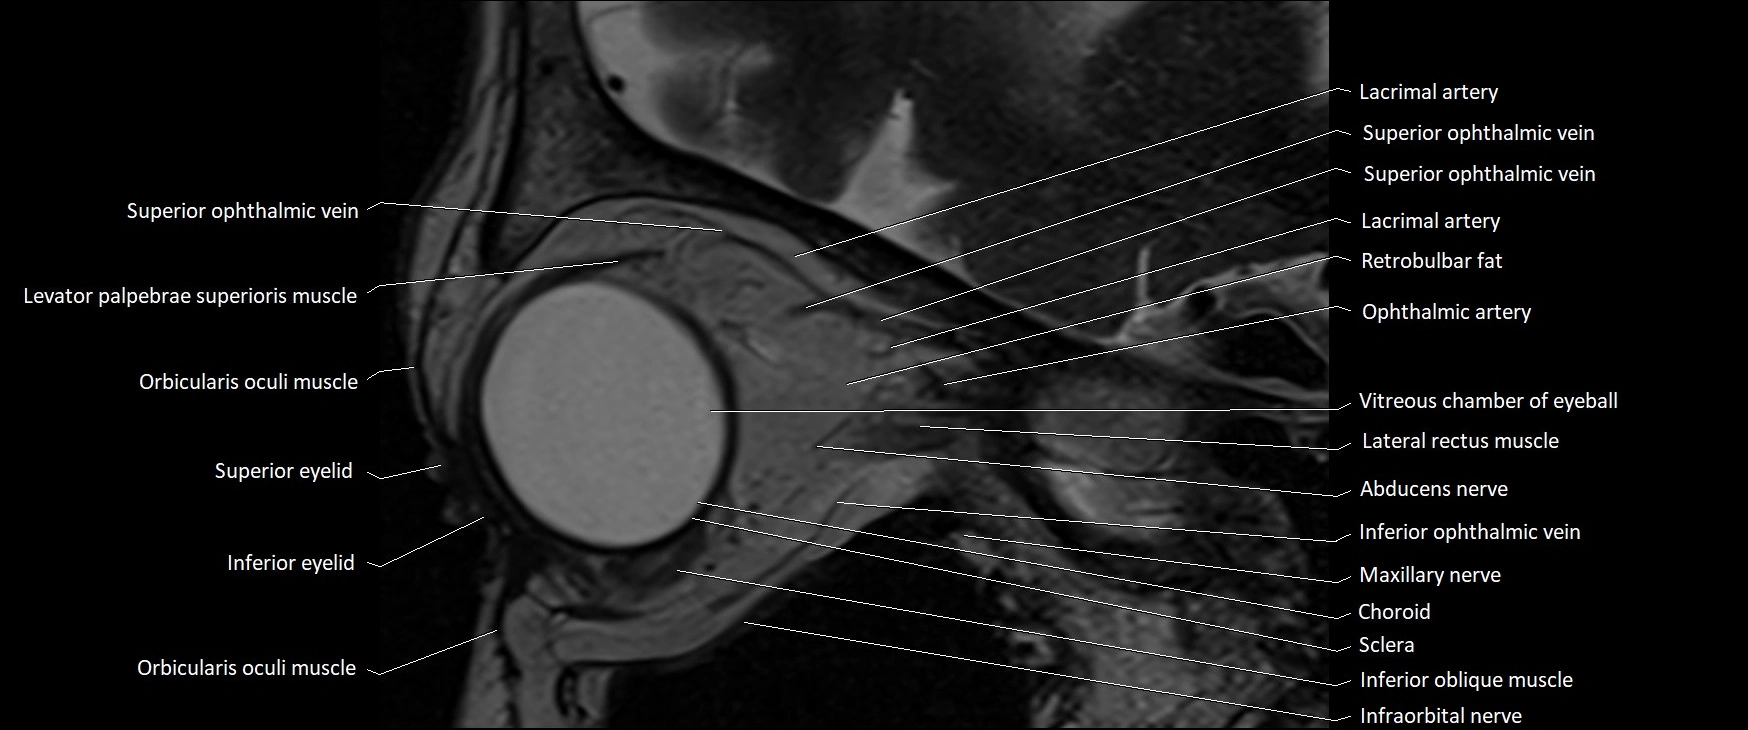

MRI images